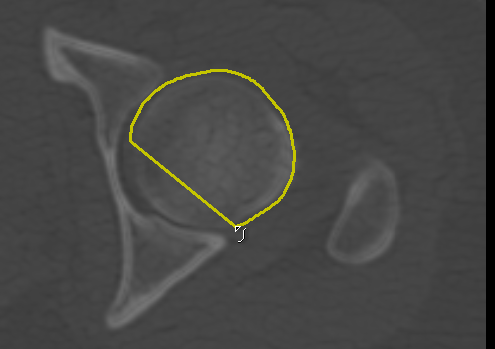

Adds a new path in Snap mode to the current group of paths. You use the Snap tool to create a path by simply dragging inside a feature on a 2D view. The contour line will automatically snap to the gradient that defines the edges of the targeted feature. Do the following to draw a path in Snap mode: